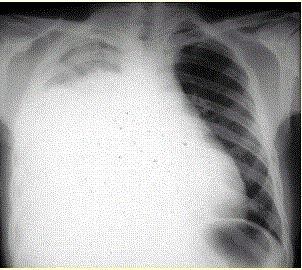

患者男,34岁。进行性胸闷、气促1个月余,伴有干咳、右胸隐痛以及消瘦,无咯血、发热、盗汗、潮热等。(提示 胸部X线检查如图所示。)患者的胸腔穿刺结...

问题 患者男,34岁。进行性胸闷、气促1个月余,伴有干咳、右胸隐痛以及消瘦,无咯血、发热、盗汗、潮热等。(提示 胸部X线检查如图所示。) 患者的胸腔穿刺结果提示胸腔积液的性质和病因最可能是(提示 患者诊断性胸腔穿刺结果:胸腔积液呈淡红色,细胞数600×10/L,单核细胞65%,蛋白32 g/L,葡萄糖1.8 mmol/L,LDH550 U/L,ADA 18 U/L,CEA 125 μg/L)

选项 A.漏出性胸腔积液 B.渗出性胸腔积液 C.低蛋白血症所致胸腔积液 D.结核性胸腔积液 E.恶性胸腔积液 F.类肺炎性胸腔积液

答案 BE